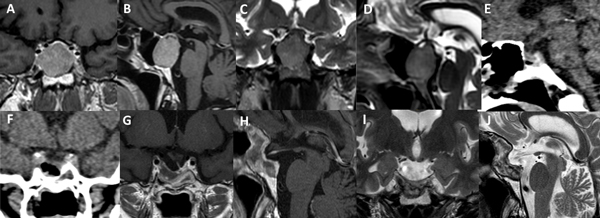

La técnica de “Guante Blanco” se indica en pacientes con macroadenomas no funcionantes, apoplejía pituitaria, enfermedad de Cushing, acromegalia, adenoma secretor de TSH y en portadores de prolactinomas con una clara indicación quirúrgica. La indicación principal es en tumores infradiafragmáticos, es decir, por debajo de la duramadre del diafragma selar o respetando el orificio del anillo dural (Figura 5). Se podría valorar a futuro su indicación en casos con extensión supraselar sin invasión ventricular y sin invasión lateral.

Existen situaciones que contraindican relativamente el uso de esta técnica y precisa un abordaje “extendido”: adenoma en reloj de arena, alto grado de extensión supraselar (e.g. invasión del III ventrículo), extensión para-selar (e.g. englobamiento carotideo), consistencia dura o fibrosa del tumor (Figura 6).

Figura 5. Paciente de 45 años con prolactinoma infradiafragmático resistente a cabergolina. Se utilizó un abordaje de Guante Blanco para su tratamiento. A-D: RM preoperatoria. E-F: TC del primer día postoperatorio. G-J: RM postoperatoria.

Figura 6. Paciente de 62 años, acromegálica, con adenoma gigante Hardy C y Knosp 4. No fue candidata a abordaje de Guante Blanco. Se utilizó un abordaje extendido para su tratamiento. A-D: RM preoperatoria. E-F: TC del primer día postoperatorio. G-J: RM postoperatoria.